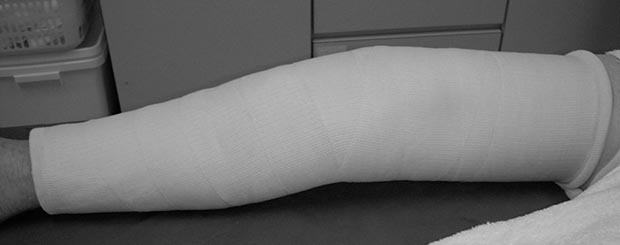

保存療法は、膝蓋骨が骨折しても、折れた骨のカケラがあまり引き裂かれなかった場合に行われます。具体的には、大腿部から足までの長いギプスを巻いて(図2)、あるいは装具という特殊な固定具を用い、膝をまっすぐに伸ばした状態で固定します。そして骨折が治った直後から膝関節の曲げ伸ばしのリハビリを行います。

図2 保存療法。大腿部から足までの長いギプスを巻く。